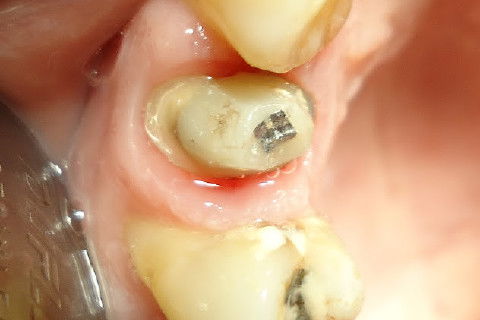

Paciente de 52 anos, gênero masculino, leucoderma.

QP: dente 14 era portador de um "pivot" que "vivia se soltando e agora não parava mais..."

- Preparo do conduto, instalação de pino rosqueável e confecção de NP em resina;